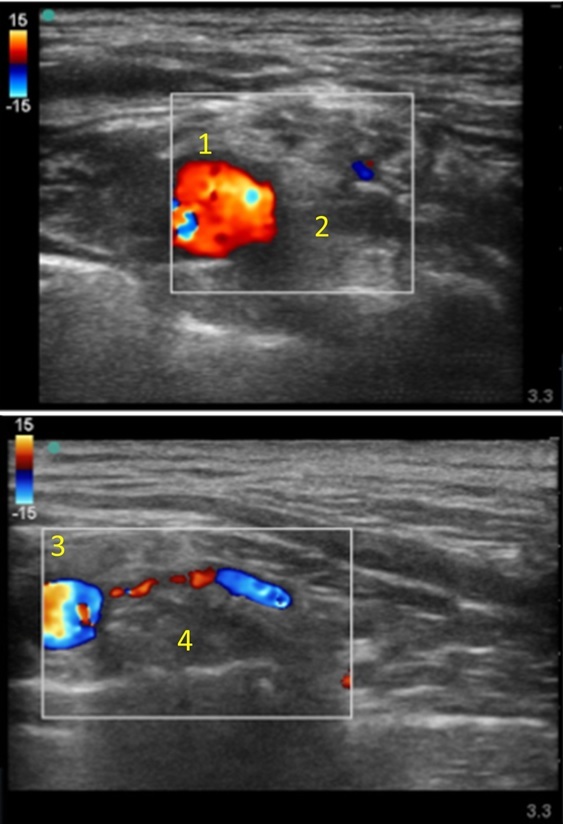

1. Subclavian Artery

2. Branch Short Axis

3. Subclavian Artery

4. Branch Long Axis